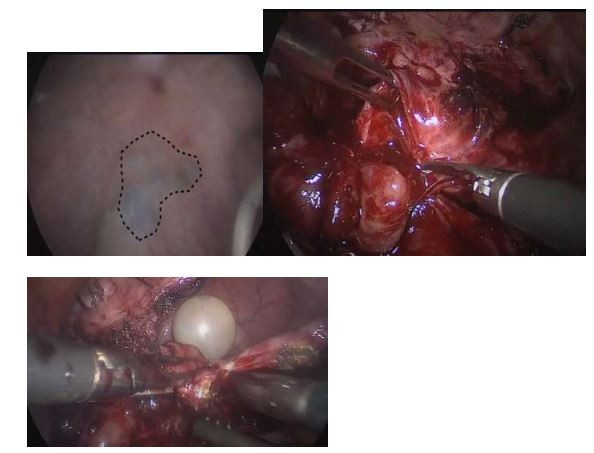

Paciente de 32 anos refere disúria, hematúria ocasional e dor pélvica cíclica. Ultrassonografia pélvica transvaginal evidenciou espessamento em região vesicouterina de 3 cm. Foi indicado tratamento cirúrgico que evidenciou a lesão demarcada na cistoscopia. Laparoscopia evidenciou a lesão, que foi removida apropriadamente. Assinale a alternativa sobre o diagnóstico e sobre o tratamento cirúrgico desse caso: